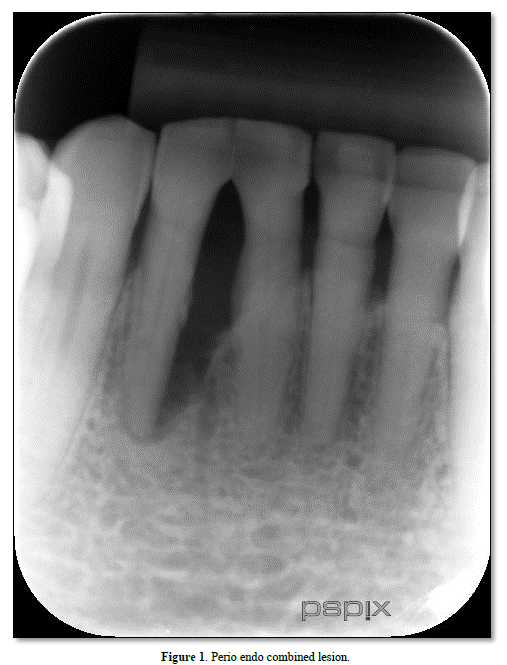

Pulpal and periodontal tissues communicate most directly through the apical foramen [8]. Bacterial and inflammatory by-products may pass through the apical foramen, leading to periapical pathosis and trigger inflammation in the periapical tissues and bone loss [7] (Figure 1).

Lateral and accessary canals may appear anywhere along the root, usually in the apical and molar furcation areas [5,8], and patent accessory canals can allow the spread of bacteria and toxins leading to inflammation and widening of the PDL [6]; (Figure 1) Gutman [9] stained 102 molar teeth in a vacuum chamber using safranin dye and found 28.4% of the teeth possessed furcation canals, although only 10.2% did so on the lateral root surface. An analysis by Rubach [10] of 74 teeth revealed that 45% had accessory canals present, primarily near the apex.